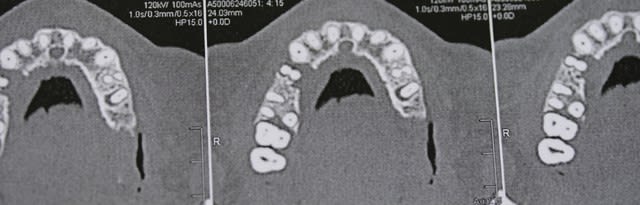

aahh enfin du lourd ! j'etais un peu jaloux pcq je ne voyais jamais de beau kystes comme sur eugenol ,et le voilà :-))

bon , là , si il y en a 1 qui me dit qu'il fait une resection apicale , il est fort :-))

mg 0745 duixhj - Eugenol

mg 0750 ntmymv - Eugenol

mg 0749 glo3ra - Eugenol

mg 0751 ydh9jm - Eugenol

mg 0752 dzsnaz - Eugenol

mg 0753 htzjhi - Eugenol

C'est là qu'on voit tout de suite l'intérêt du pano. -)